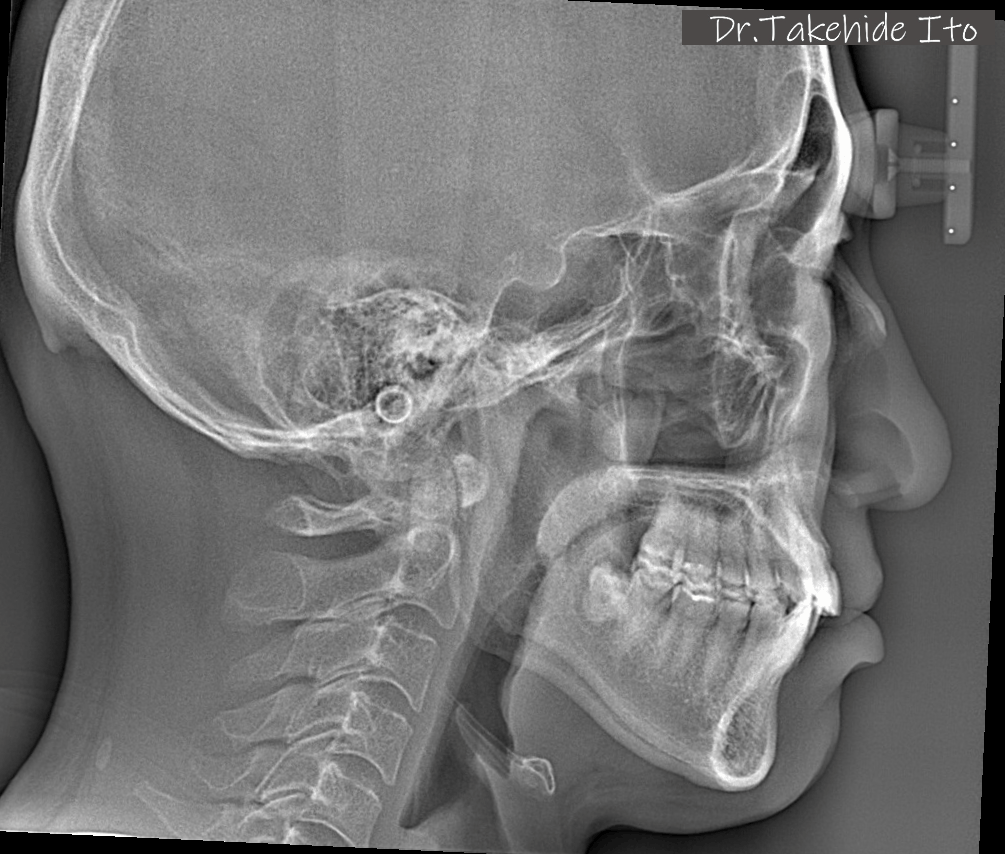

黒飛の実際のセファロで

診査する伊藤剛秀先生

伊藤先生の診査を受け、セファロとiTeroの結果、腰痛の根本原因が「顎位のズレ」にあることが判明。そこからマウスピース治療を開始したことで、長年の悩みの種であった腰痛が劇的に改善。